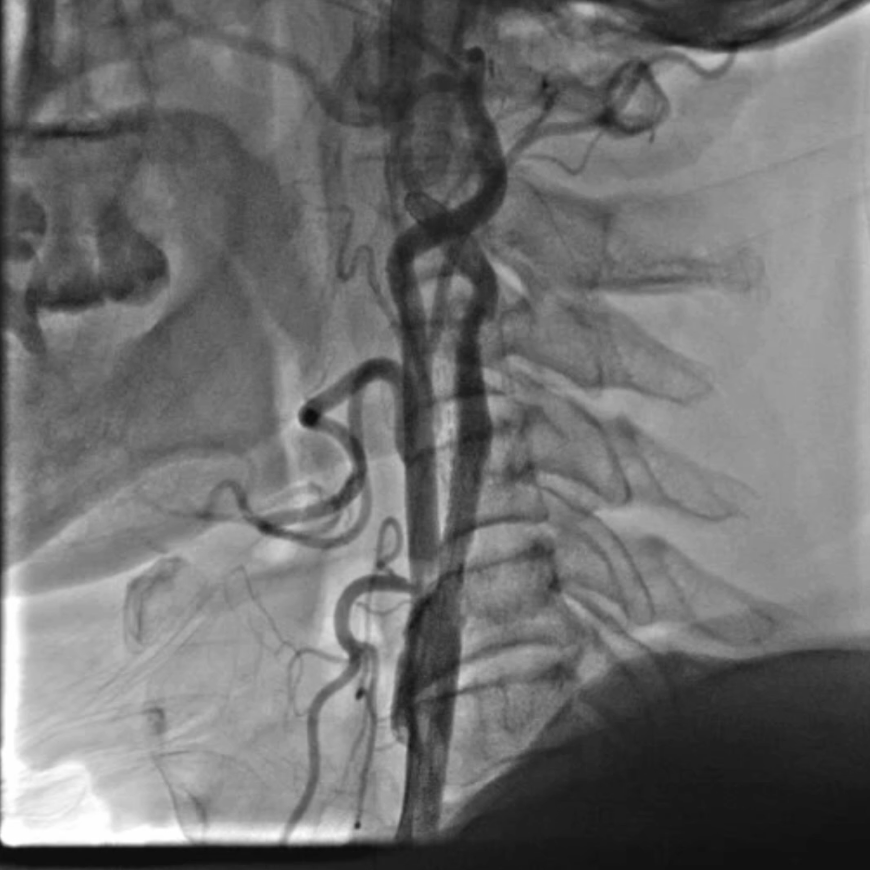

颈动脉超声:左侧颈内动脉重度狭窄(峰值流速325cm/s,狭窄率>70%),右侧颈内动脉完全闭塞;

CTA:主髂动脉完全闭塞,钙化严重。

CTA

通路建立:精准操作减少血管损伤

穿刺与鞘管置入:局麻下穿刺右侧桡动脉,置入6F动脉鞘;

导管塑形与定位:使用SIMMONS导管选择左侧颈总动脉,操作时需轻柔(避免导管头端触碰血管壁导致斑块脱落),通过“反八字”塑形可精准对接左侧颈总动脉,导管弯部挂于颈动脉分叉处提供稳定支撑;

长鞘置入:在左前斜位透视下送入90cm长鞘,全程观察方向以避免阻力过大导致血管损伤